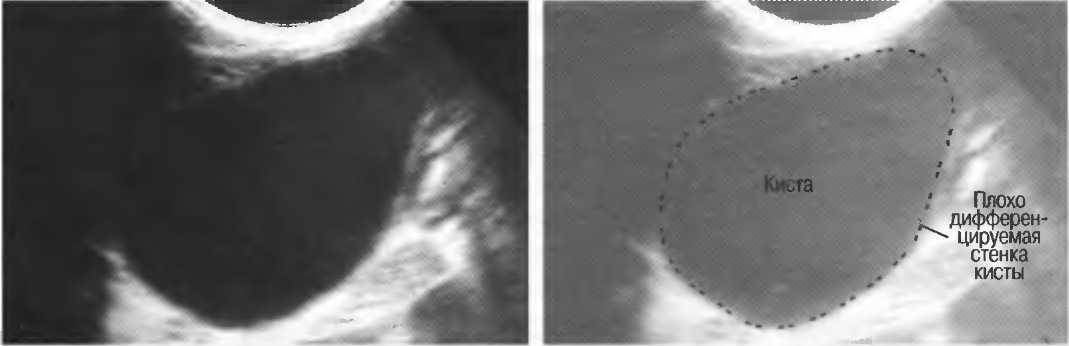

Кисты

Киста, как правило, визуализируется в виде анэхогенной зоны, при этом структуры, расположенные за кистой, обычно усилены: полость кисты анэхогенна, поскольку в ней нет структур с различным акустическим сопротивлением. В результате того что жидкость не поглощает ультразвук в такой же степени, что и ткань, эхо-сигналы от расположенных позади кисты структур гиперкомпенсированы сканером и выглядят усиленными — появляется эффект усиления задней стенки (рис. 14а,б).

Киста определяется в виде анэхогенной зоны с усилением по задней стенке. Если в кисте есть внутренние зхоструктуры, то они могут быть реальными или являться артефактами.

Рис. 14а. Заполненная жидкостью киста: полость кисты анзхогенна, имеется усиление задней стенки.

Рис.14б. Данная киста яичника имеет толстые стенки и внутренний осадок, создающий внутреннюю эхоструктуру, перемещающуюся при перемене положения тела пациента.

Если уровень чувствительности прибора достаточно низок, солидное образование может выглядеть кистозным. Но при этом нет усиления задней стенки (нет дорсального усиления).